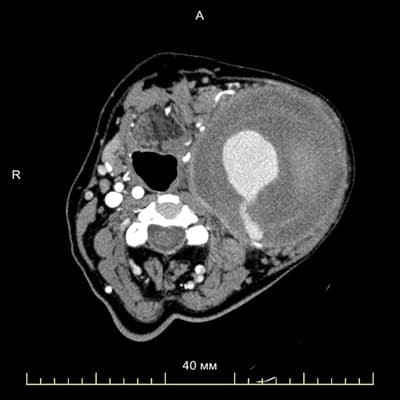

Для того чтобы определить объем вмешательства и правильный выбор доступа, была выполнена мультиспиральная компьютерная томография с контрастированием грудной аорты и сосудов шеи.

Первоочередная задача, которая стояла перед нами, — спланировать, каким доступом лучше добраться до пораженного участка сонной артерии и безопасно отделить аневризму, не повредив другие структуры.

Аневризма была плотно сращена с окружающими тканями, ее отделение от других сосудов, нервов, мышц гортани, подчелюстной области шейного отдела позвоночника выглядело достаточно сложным.

К тому же аневризма не была полностью тромбирована, кровоток в ней присутствовал, и малейшее ее повреждение при проведении операции могло вызвать профузное кровотечение. Поэтому для обеспечения доступа не исключали выполнение стернотомии с пережатием левой общей сонной артерии для контроля.